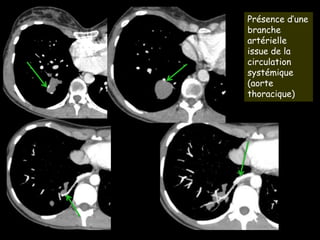

Présence d’une

branche

artérielle

issue de la

circulation

systémique

(aorte

thoracique)

Présence d’une branche

artérielle issue de la

circulation systémique

(aorte thoracique)

• Jeune femme

• Infections pulmonaires à répétition

• Actuellement asymptomatique, apyrétique

• Masse lobaire inférieure droite

• Exclue de l’arbre bronchique

• Vascularisée par un vaisseau issu de l’aorte thoracique

séquestration pulmonaire intra-lobaire

de type Pryce 3